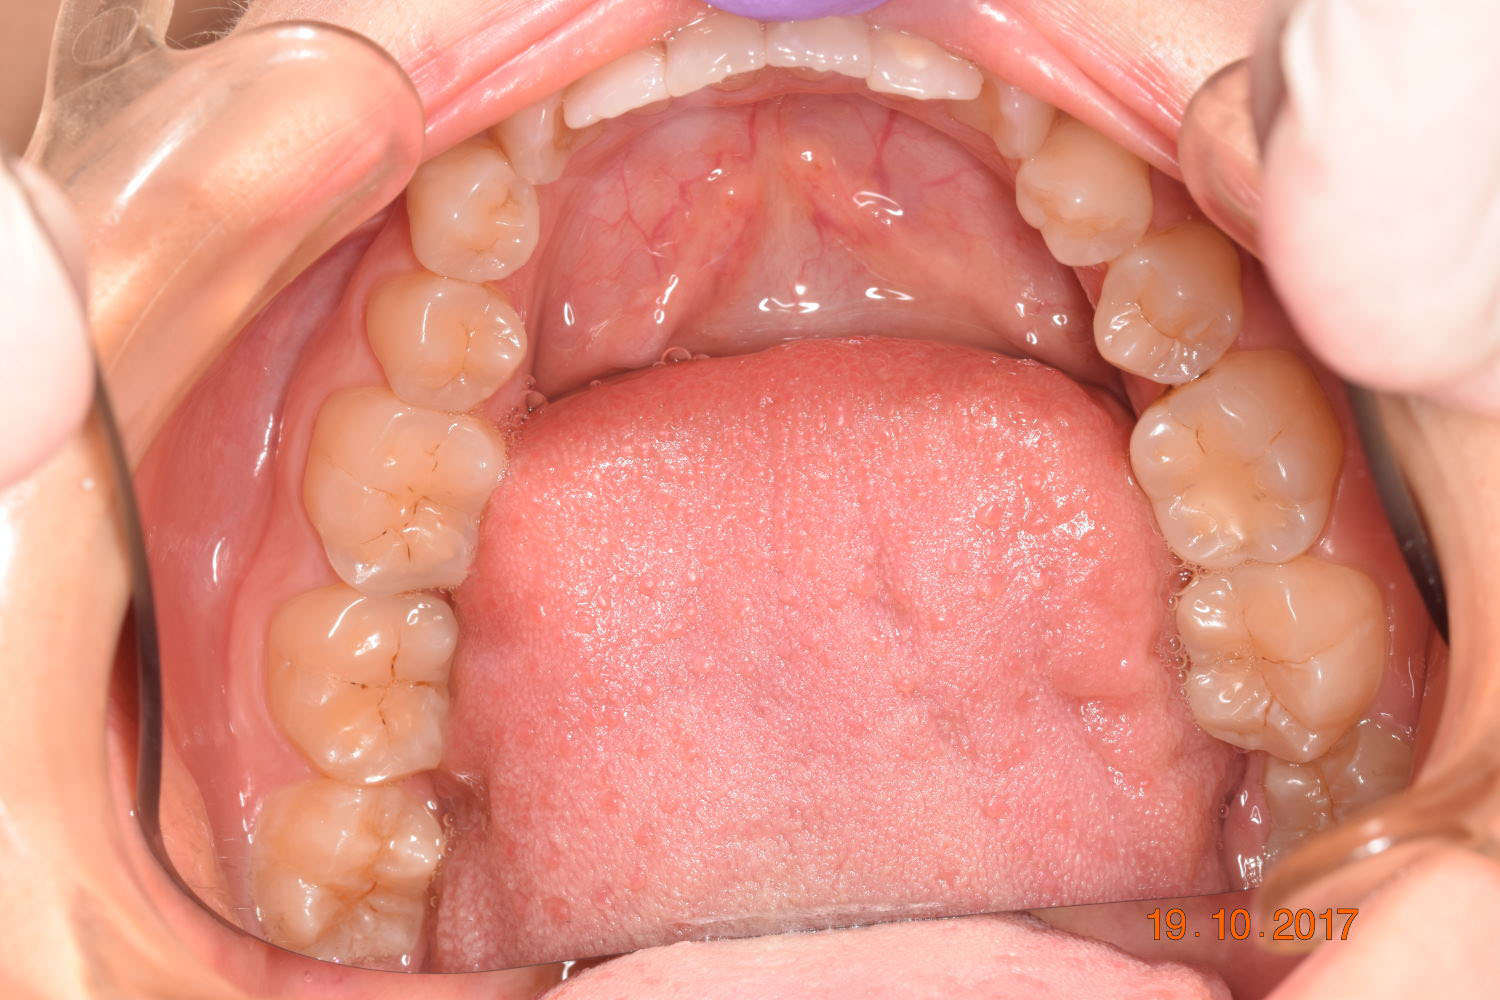

A 27-year-old female patient presented with class III malocclusion, 15 mm crowding in the upper arch, an anterior open bite, a lateral crossbite, and a total ABO score of 29. Her facial profile was straight with a retrusive maxilla, and the upper and lower incisors were retroclined. An extreme lack of midface support was also noted, and the constricted dental arches resulted in a poor smile width and dark buccal corridors. No myofunctional investigations were performed at the time, as they were initially considered unnecessary.

Adhering to the principles of Face First Orthodontics, the primary objective was to increase midface support by expanding the upper maxilla, fixing the cross bite, and aligning the teeth. Closing the open bite was a secondary objective.

Dr. Coca’s treatment plan followed the Biology First Orthodontics approach, which aims to minimize biological interventions. The treatment plan avoided extractions, stripping, TADs, corticotomy, and RPE. Given the facial requirements, a non-extraction treatment option was chosen.

The treatment began in 2017. Given the patient’s preference for less visible brackets, Damon Clear brackets were selected. High torque upper cuspids and low torque upper incisors were chosen to offer the best torque control for upper arch development. For the lower arch, there were no alternative bracket configurations available. Bite turbos were applied to the upper second molars.